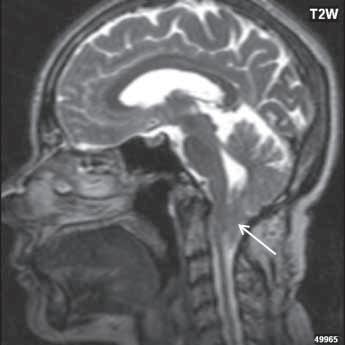

Chiari I: CT a MR zobrazí malou zadní jámu lební, absenci cisteren zadní jámy lební, pokles tonzil, krátký a konkávní klivus, poruchu cirkulace mozkomíšního moku v oblasti foramen magnum a následný hydrocefalus. MR navíc může prokázat edém krční míchy a ve vysokém procentu případů hydrosyringomyelii.

Chiari II: CT a MR zobrazí malou zadní jámu lební, absenci nebo výraznou redukci cisterny cerebelomedulární a dalších kmenových cisteren, konkávní klivus. Mohou být abnormality v oblasti foramen okcipitale magnum, nízký úpon tentoria, někdy absence nebo fenestrace falx cerebri. MR lépe ukáže kaudálně uloženou a protáhlou IV. komoru (někdy je přirovnávána až ke stéblu slámy), protažený pons a další možné, přidružené abnormality (hydrosyringomyelii, agenezi, hypogenezi nebo fenestraci corpus callosum…).

Obr. I.1.7a Sestup mozečkových tonzil (šipka), Chiariho malformace I

Obr. I.1.7b Sestup mozečkových tonzil, „pek like“ (šipka), Chiariho malformace I c d

Sestup mozečkových tonzil,